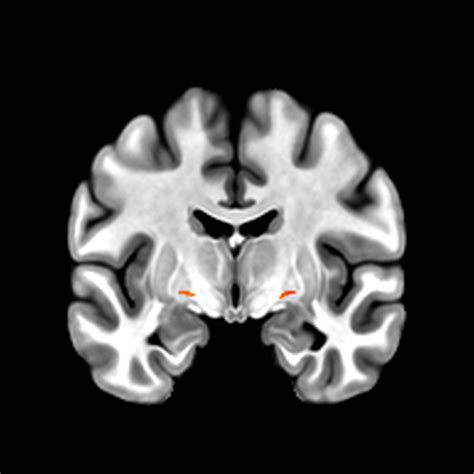

• Neuroimaging: Techniques such as magnetic resonance imaging (MRI) and positron emission tomography (PET) can visualize the structure and activity of the BNM. These imaging methods help identify atrophy, inflammation, or other abnormalities in the BNM.

In addition to these techniques, emerging technologies such as functional MRI (fMRI) and diffusion tensor imaging (DTI) offer more detailed insights into BNM connectivity and function. These advanced imaging methods can help researchers and clinicians better understand the role of the BNM in health and disease.